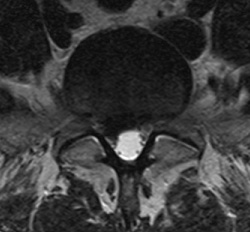

Axial T2 weighted image of the lumbar spine. The same L5-S1 disc extrusion, is displacing and compressing descending left S1 nerve root.